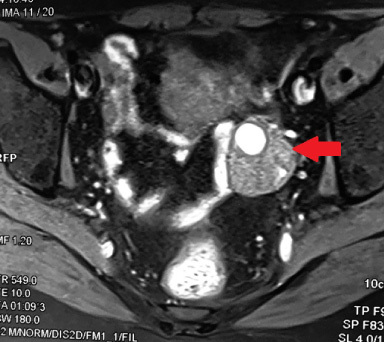

Primary angiosarcoma (PAS) of the breast is an extremely uncommon variant of breast malignancies. Highly aggressiveness and dismal prognosis characterize this endothelial neoplasm. We report here an unusual case of PAS of the breast occurring in a 46-year-old woman associated with concurrent bilateral invasive ductal carcinoma and ovarian metastases.